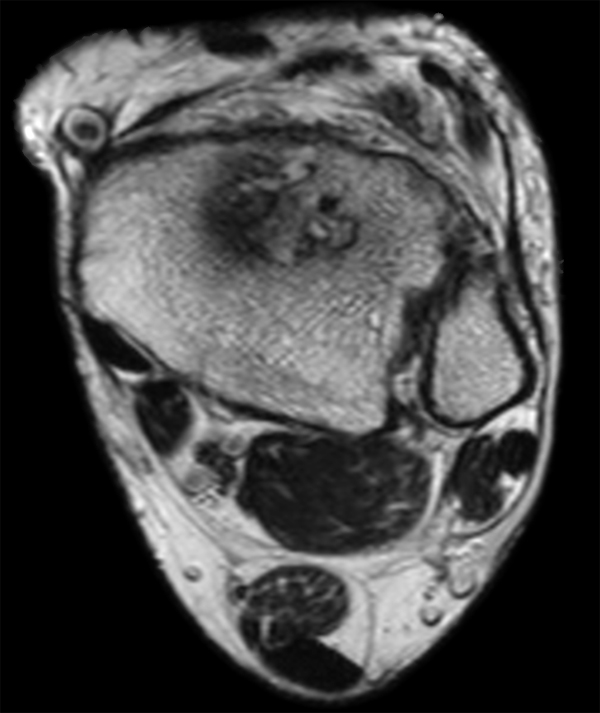

Axial PDW TSE